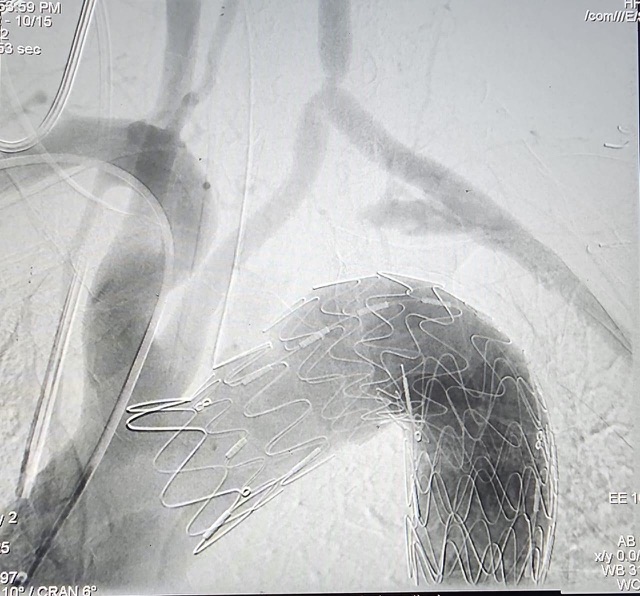

وأشار البيان إلى أنه على الفور اجتمع فريق جراحة الأوعية الدموية بالمستشفى لدراسة الحالة، وجرى تحديد الإجراءات الطبية اللازمة، وتم إتخاذ قرار اجراء الجراحة بتقنية التيفار TEVAR.

ويعد هذا النوع الحل الأمثل لتلك الحالات، ما يعني أنه يعتمد على استخدام القسطرة التداخلية، من خلال شقوق جراحية صغيرة، والتي تساعد بدورها على تخفيف ألم الصدر والأعراض الأخرى، وتم التواصل مع شركات توريد تلك الدعامات لتحديد قياسات الدعامات اللازمة للحالة بدقة وتجهيزها.

وأوضح البيان، أنه تم إجراء الجراحة للسيدة عن طريق تركيب دعامات مغطاه بالشريان الأورطى بالصدر، باستخدام القسطرة التداخلية مع توصيل الشريان السباتي الأيسر بالشريان تحت الترقوة اليسرى جراحيا باستخدام شريان صناعي.